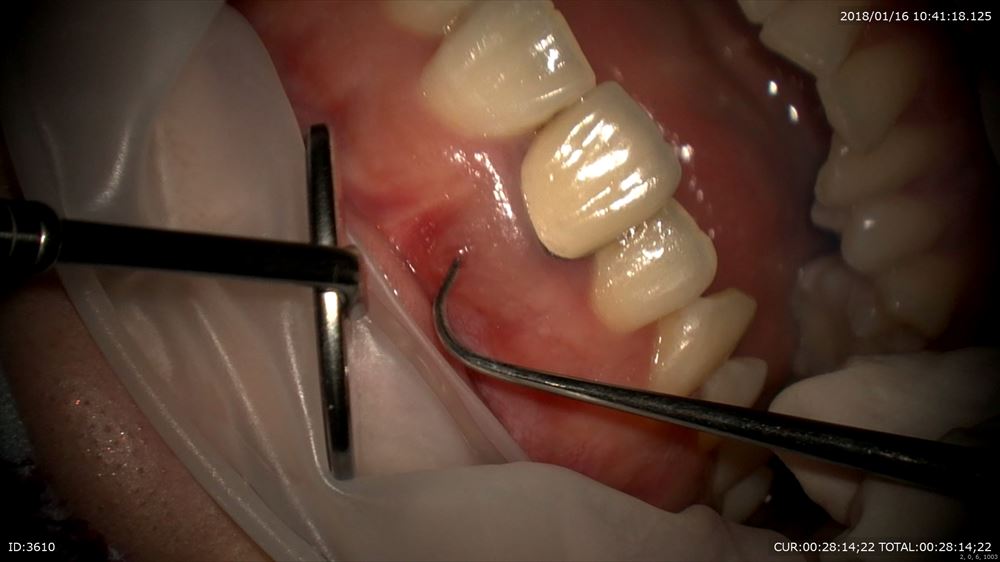

「被せ物を他院でした歯の歯茎にできものができた。」

精密仮歯が重要。治療中も細菌感染を防ぐ為です。外していきます。

やっぱり銀歯虫歯。ここから最近感染がおきて根管が感染したと思われます。感染を染めて